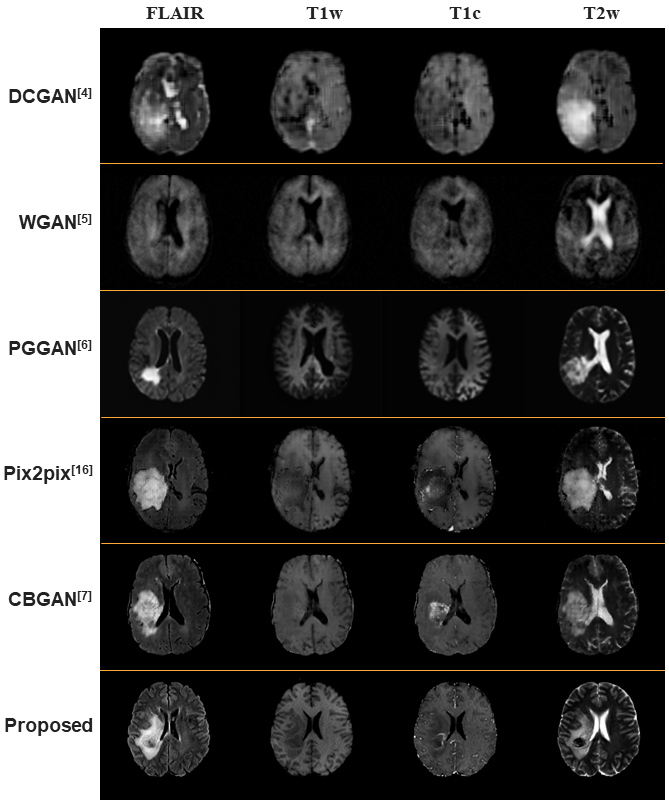

Figure 8: Comparison of brain tumor images synthesized by various augmentation methods.

4.3 Comparisons with Other GAN Methods

The results produced by the proposed method are compared with those produced by other GAN-based synthesis methods in Fig.8. The first three rows are results of the unconditional GAN-based methods, which use random noise as an input, namely, DCGAN, WGAN, and PGGAN. As mentioned earlier, DCGAN is simple to train, but the results of DCGAN are unstable and unrealistic. The results generated by WGAN, on the other hand, are sharper, but unstable too. PGGAN is the best performance generative algorithm among the unconditional GANs, and brain tumor images are synthesized realistically. However, these unconditional GAN-based methods can only synthesize brain tumor images, not grade tumor masks, both of which are necessary for the training of supervised learning networks.

The 4th and 5th rows show the results of Pix2pix and CBGAN, respectively, where the brain tumor images were synthesized from the brain tumor label maps. Their results seem relatively unnatural because the normal parts must also be synthesized and the loss functions of their methods may not be sufficient. In the case of Pix2pix, there are lattice artifacts due to GAN’s instability. In the case of CBGAN, similar to our proposed method, it uses various loss functions to remove lattice artifacts and to have learning stability. However, the non-tumor parts are displayed unnaturally compared to the proposed method. The proposed method fills the non-tumor part with the normal brain image as it is and generates only the tumor part. Thus, the results of the proposed method look most realistic.